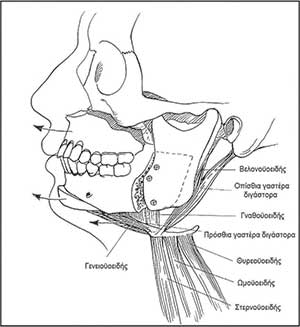

Εικόνα 3

Εποµένως, για την οριστική χειρουργική αντιµετώπιση του ΣΑΑΥ µε σκοπό την ίαση, η επέµβαση που ενδείκνυται είναι η αµφιγναθική προώθηση του γναθοπροσωπικού συµπλέγµατος (Maxillo Mandibular Advancement – MMA – Εικόνα 3).

Σύµφωνα µε διεθνή βιβλιογραφικά δεδοµένα των 2 τελευταίων δεκαετιών, οι χειρουργικές επεµβάσεις που προβλέψιµα µπορούν να απαλλάξουν τους ασθενείς από την ανάγκη µη επεµβατικού µηχανικού αερισµού είναι οι προωθητικές οστεοτοµίες του σπλαγχνικού κρανίου. Αυτές γίνονται στην άνω γνάθο σε επίπεδο LeFort I για την ανακούφιση οπισθοϋπερώιας απόφραξης του αεραγωγού, διευρύνοντας έµµεσα τον φαρυγγικό αυλό πίσω από τη µαλακή υπερώα. Στην κάτω γνάθο διενεργούνται οβελιαίες οστεοτοµίες των κλάδων αµφοτερόπλευρα για την προώθηση του οδοντοφόρου τµήµατος της κάτω γνάθου και τη διεύρυνση του στοµατοφαρυγγικού αυλού πίσω από τη βάση της γλώσσας στο οπισθογλώσσιο τµήµα του. Στο γένειο µπορεί να γίνει µια οριζόντια γενειοτοµή για την προώθηση του κάτω χείλους της γενειακής σύµφυσης, συµπεριλαµβάνοντας τις γενειακές άκανθες που είναι τα καταφυτικά πεδία των γενειογλωσσικών µυών. Οι γενειογλωσσικοί µύες είναι οι κυριότεροι διαστολείς του φαρυγγικού αεραγωγού. Οι µετατοπίσεις είναι σηµαντικές (της τάξεως των 10 mm) και για να µην προκύπτουν διαταραχές της οδοντικής σύγκλεισης µετεγχειρητικά, απαιτείται στις περισσότερες περιπτώσεις προεγχειρητική ορθοδοντική προετοιµασία, καθώς και διενέργεια οστεοτοµιών σε άνω και κάτω γνάθο σε συνδυασµό.